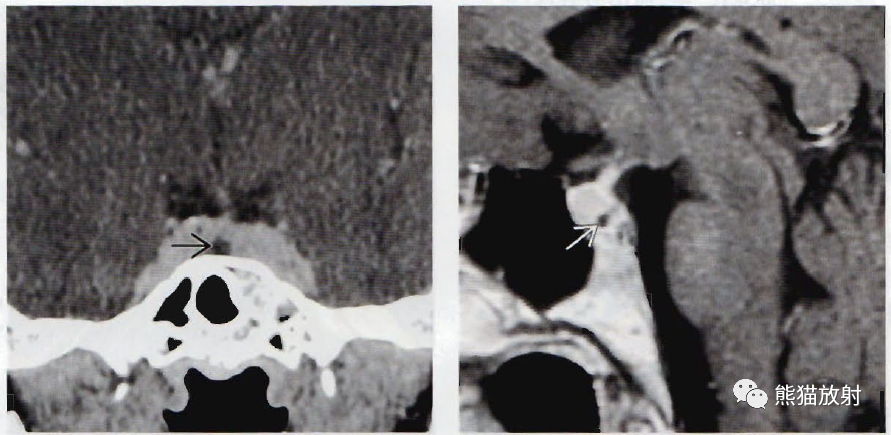

(左)冠状位图显示小的微腺瘤(箭)使右侧垂体轻度扩大,漏斗左移。

(右)冠状位显微病理学显示正常垂体包绕一小的无功能微腺瘤,为尸检偶然发现。